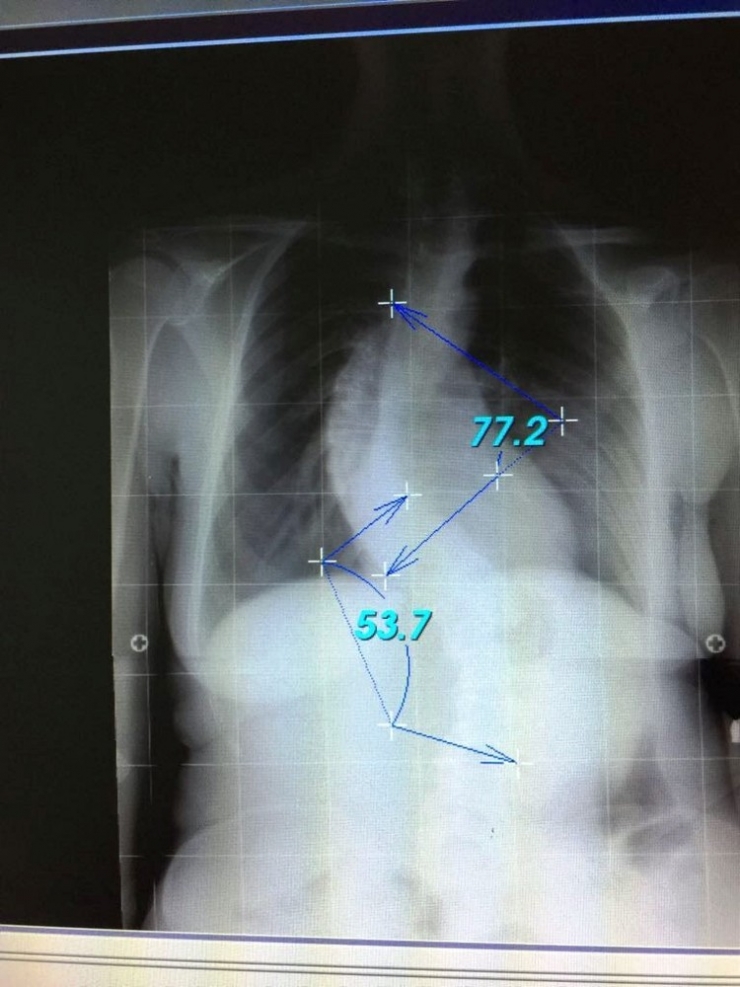

Genelde 45-50 derecenin üzerinde olan eğriliklerin ergenliğin bitip büyüme tamamlansa bile ilerlemeye devam ettiğini söyleyen Önder, "İlerleme sırtta ve belde estetik olarak kötü bir görüntü oluşturduğu gibi akciğer fonksiyonunu da bozabilir. Bu durumda skolyoz cerrahisi yapan çoğu doktor skolyoz eğriliğini azaltmak ya da artmasını engellemek için cerrahi tedaviyi tercih eder. Büyümesi devam eden bir çocukta 40-50 derece arasında skolyoz eğriliği varsa bir çok faktör değerlendirildikten sonra ameliyata karar verilmelidir. Omurganın normalden fazla öne eğilmesine kifoz (kamburluk) diyoruz. Sıklıkla 9-12 yaşlarındaki çocuklarda hızlı büyüme devresinde öne doğru eğilmeleri sonucu omurga kemiklerinin gelişimi bozulup kamalaşmalar oluşmaktadır. Onun için ilkokul öğretmenlerine beden eğitim öğretmenlerine ve başta ailelere çocukların normal pozisyonda durmalarını sağlayacak bilgiler verilmektedir. İleri derecede olan kamburluklar kişinin fonksiyonunu bozmakta. Erkek çocukları askerlik yapamamaktadır. Onun için postür (duruş) bozukluluğu olan çocukların erkenden doktora götürmeleri sadece egzersiz veya özel cihazlarla kamburluk önlenebilmektedir. Geç kalan durumlarda kamburluk derecesi artanlarda tedavi cerrahidir. Bununda hastaya, aileye ve devlete faturası büyük olmaktadır" şeklinde konuştu.